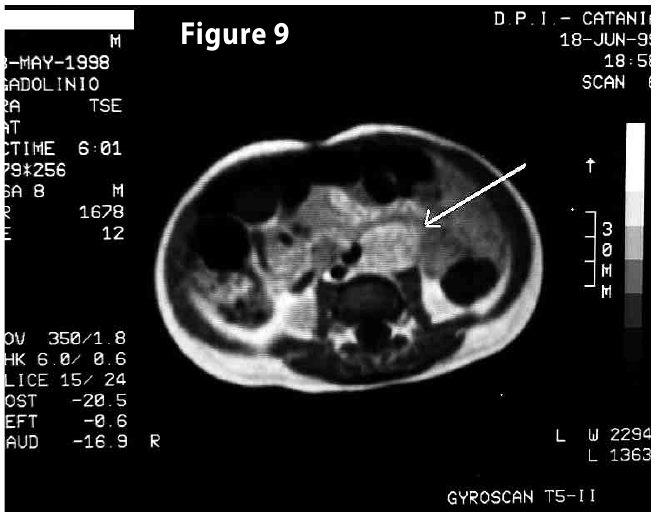

Complete objective response of neuroblastoma to biological treatment.

Figure9